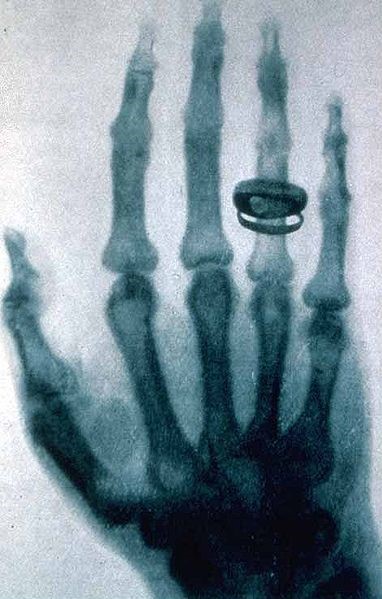

Röntgen non aveva documenti per far conoscere la sua scoperta e fu allora che pensò di utilizzare le lastre fotografiche per documentare la sua scoperta. Si trattava solo di sostituire la lastra ricoperta di platinocianuro di bario con una lastra fotosensibile ed ottenne risultati superiori ad ogni aspettativa. Per documentare

ciò chiese a sua moglie, Anna Bertha Ludwig, di disporre la sua mano sulla lastra fotografica e così si ottenne la prima radiografia nota della storia. Röntgen preparò una breve memoria di 10 pagine accompagnata da alcune foto che consegnò al

Radiografia della mano di Anna Bertha Ludwig Röntgen

segretario della Società di fisica medica di Würzburg. La memoria fu pubblicata il 28 dicembre 1895(9).